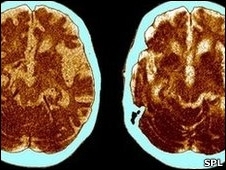

O encolhimento do cérebro é um dos sintomas da debilidade cognitiva leve que pode ser um dos indicadores iniciais de demência.

O cérebro de uma pessoa com mais de 60 anos encolhe, em média, a um ritmo de 0,5% ao ano. O cérebro das pessoas que sofrem de debilidade cognitiva leve encolhe a um ritmo duas vezes mais rápido. Nos pacientes de Alzheimer, este ritmo chega a 2,5% ao ano.